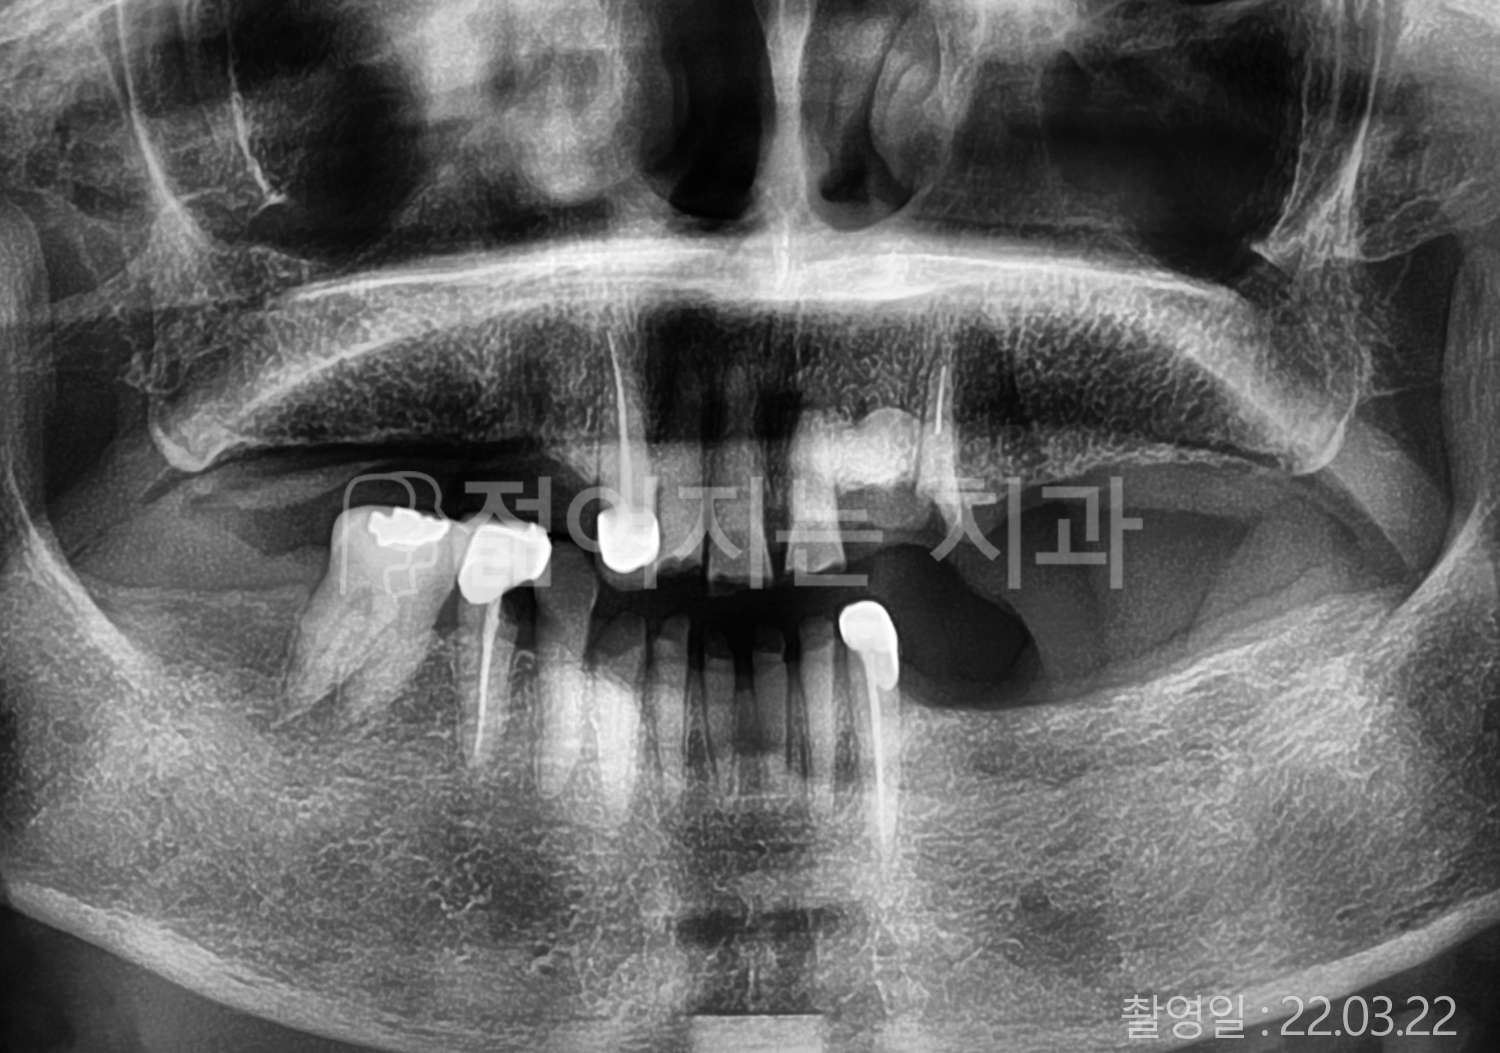

• 70대 고혈압, 암, 갑상선 질환 전체치아 10개 이상 임플란트

• 60대 고혈압, 당뇨, 고지혈증 전체치아 10개 이상 임플란트

• 40대 당뇨 전체치아 10개 이상 임플란트

• 60대 당뇨 전체치아 10개 이상 임플란트

• 70대 고혈압, 당뇨 전체치아 10개 이상 임플란트